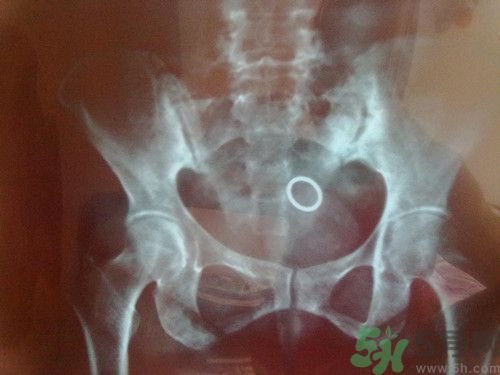

今天微博都被周杰倫患脊柱炎的消息刷爆了,脊柱炎到底是什么病呢?聽著好嚴(yán)重的樣子?能不能治好呢?下面我們來一起看看具體內(nèi)容!

1.強直性脊柱炎。年輕人發(fā)病多,一般不超過三十歲,男性多于女性。